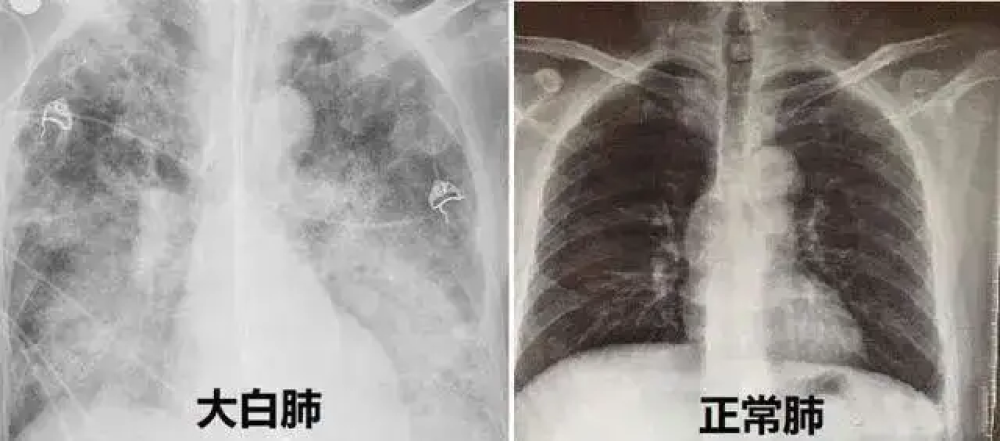

另一些人则被新闻反复提及的“白肺”吓的够呛,也开始自我怀疑,我不会“白肺”了吧?要不要去做个CT呢?

由于有这种想法的人很多,真的跑去做CT的人也很多,上海第八人民医院仅在12月27日一天,就有649人做CT。于是“阳康后要不要做CT”的话题也迅速登上了热搜,被搜索的次数高达上亿次。